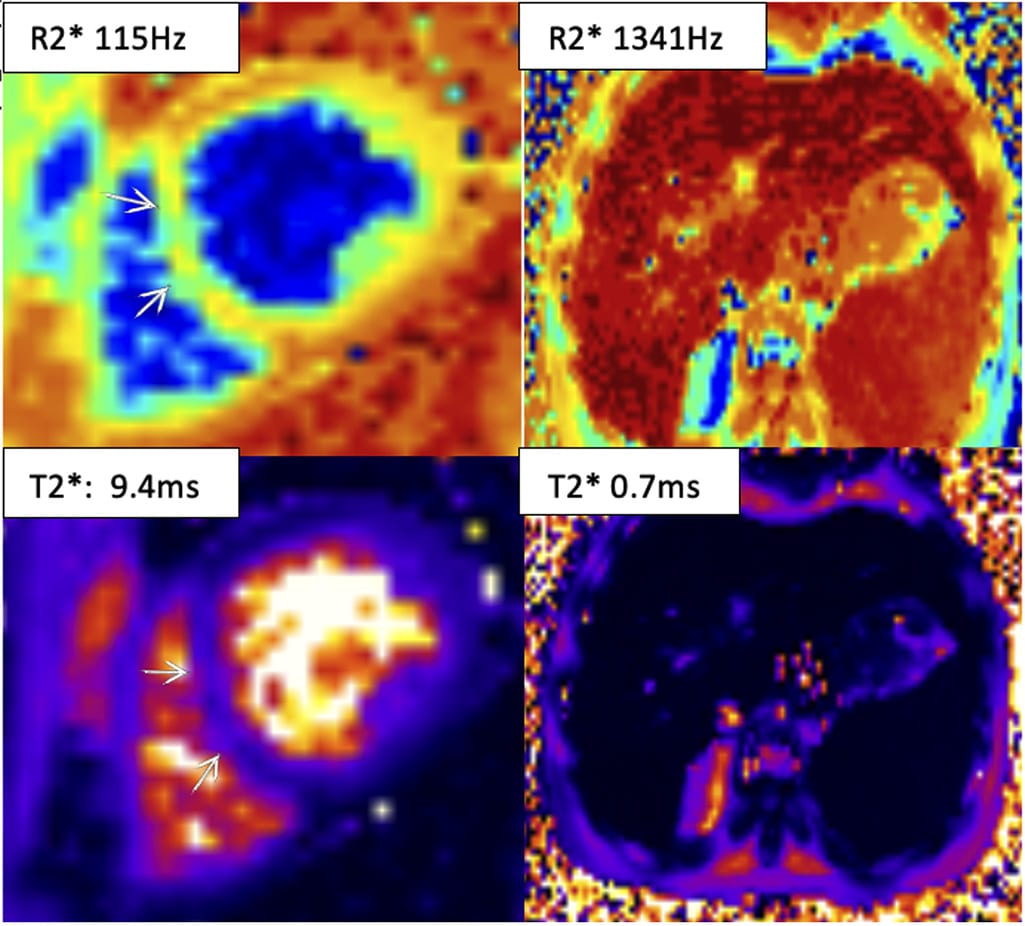

La caracterización tisular de miocardio con T2*, R2* (secuencias de libre respiración) y mapeo T1 demuestra que el hierro cardíaco está entre los niveles de moderado a severo, con medición de T2* en el septo medio de VI en 10.2ms, pero se sugiere tener en cuenta que el T2* del septo es mejor que en los otros segmentos (la medición de T2* en las paredes anterior, inferior y lateral son menores, con T2* entre 6 a 8ms) por lo que esto indica que en general el valor de hierro cardiaco es más cercano a severo de lo que parece. El valor de T1 mapa nativo en el miocardio estuvo también disminuido en 721ms (con medición de T1 en sangre de 1635ms). El valor de mapeo R2* en el septo también tiene tendencia a severidad en 101Hz. La medición de T2* (método truncado) en el hígado sugiere depósito severo (T2*: 0.7ms).

Imagen 2

RMC control demuestra tamaño biventricular normal y función sistólica preservada. Dilatación leve de aurícula izquierda. El depósito de hierro cardíaco ha empeorado ligeramente, ahora en rango de severo (específicamente la medición del septo es menor ahora, T2*: 9.4 ms) y la medición en las otras paredes se mantienen bajos entre 6-8 ms). T1 mapa nativo también ha bajado ligeramente en 699ms (con medición de componente sangre de mapa T1 normal en 1511ms). Mapeo de R2* también demuestra incremento de depósito de hierro, ahora severo (115Hz). El depósito de hierro en el hígado también sigue severo con T2* en 0.7ms.

Imagen 3

– Un valor de T2* menor 10ms como en este caso nos indica una sobrecarga severa de hierro en el miocardio, lo cual es un indicador de alto riesgo para arritmias e insuficiencia cardíaca. Esto se debe a que los depósitos de hierro en el músculo cardíaco alteran el campo magnético, provocando una rápida desintegración de la señal T2* (acortamiento). Un valor de T2* inferior a 10 ms es un factor de riesgo significativo para eventos cardíacos.

– Los mapas de T1 y R2* (en adición a T2*) también pueden ser utilizados para evaluar la sobrecarga de hierro, y la evidencia en apoyo de estos métodos alternativos está aumentando. Estas secuencias de mapeo pueden ayudar a evaluar el depósito de hierro en los diferentes segmentos y hacer un cálculo global, como en este caso que en la primera RMC se reportó severo a pesar de que el T2* septal era > 10ms.